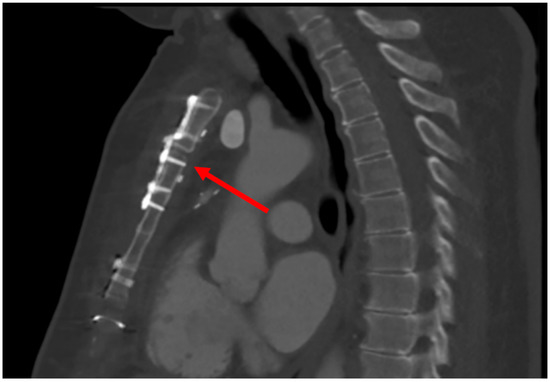

4.1.1. Case 1

4.1.2. Case 2